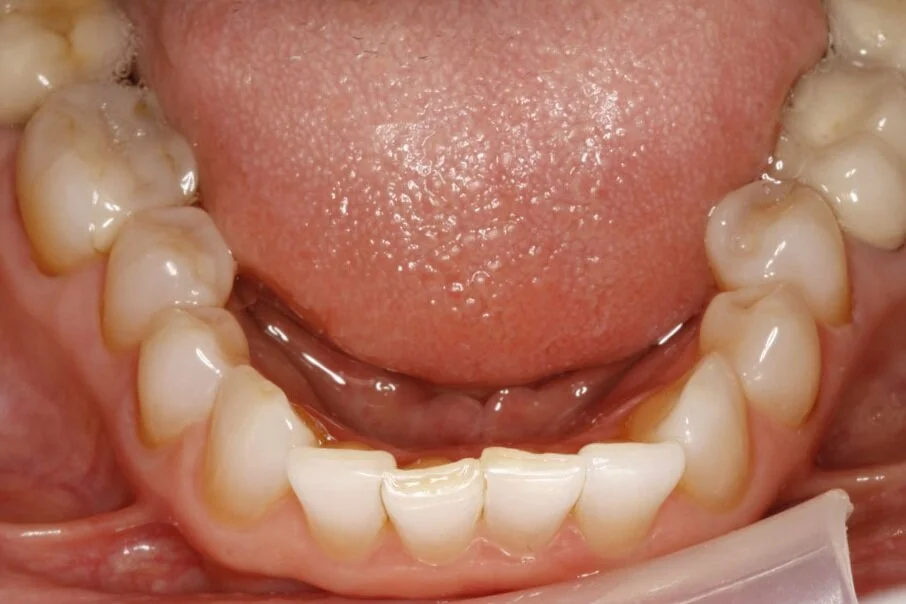

Gallery Dental Designs Roseville, CA Teeth Whitening Roseville Professional dental services in roseville, ca and greater sacramento area. Teeth whitening, root canals, cosmetic dentistry, implants and more. Whitening in roseville, lincoln, and neighboring areas. Teeth whitening is a cosmetic dental procedure designed to lighten the color of your teeth and remove stains and discoloration. If you want to enhance your smile's appearance, professional teeth whitening may be the. Teeth Whitening Roseville.